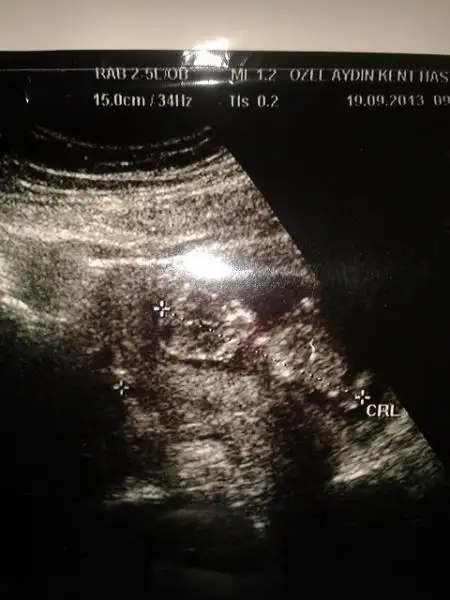

merhaba arkadaşlar elımde son ultrasyon görüntüsü yok ama bu resım var burdan anlaşılır mı? anlaşılırsa size zahmet bı yorum yapın teyzeleriiMerakla cevaplarınızı beklıyorummm

Resim çok kucuk yanılma payıyla birlikte ben erkek diyorum Hayırlısı olsun.

Canım bebegın yan yatmış sanki o yüzden yorum yapamadım. ama bir çıkıntı gibi birsey var ayak kemiği fln değilse epey inceledim erkek diyorum canım (görünen çıkıntı nubsa tabi) Gönlündeki olsun canım.